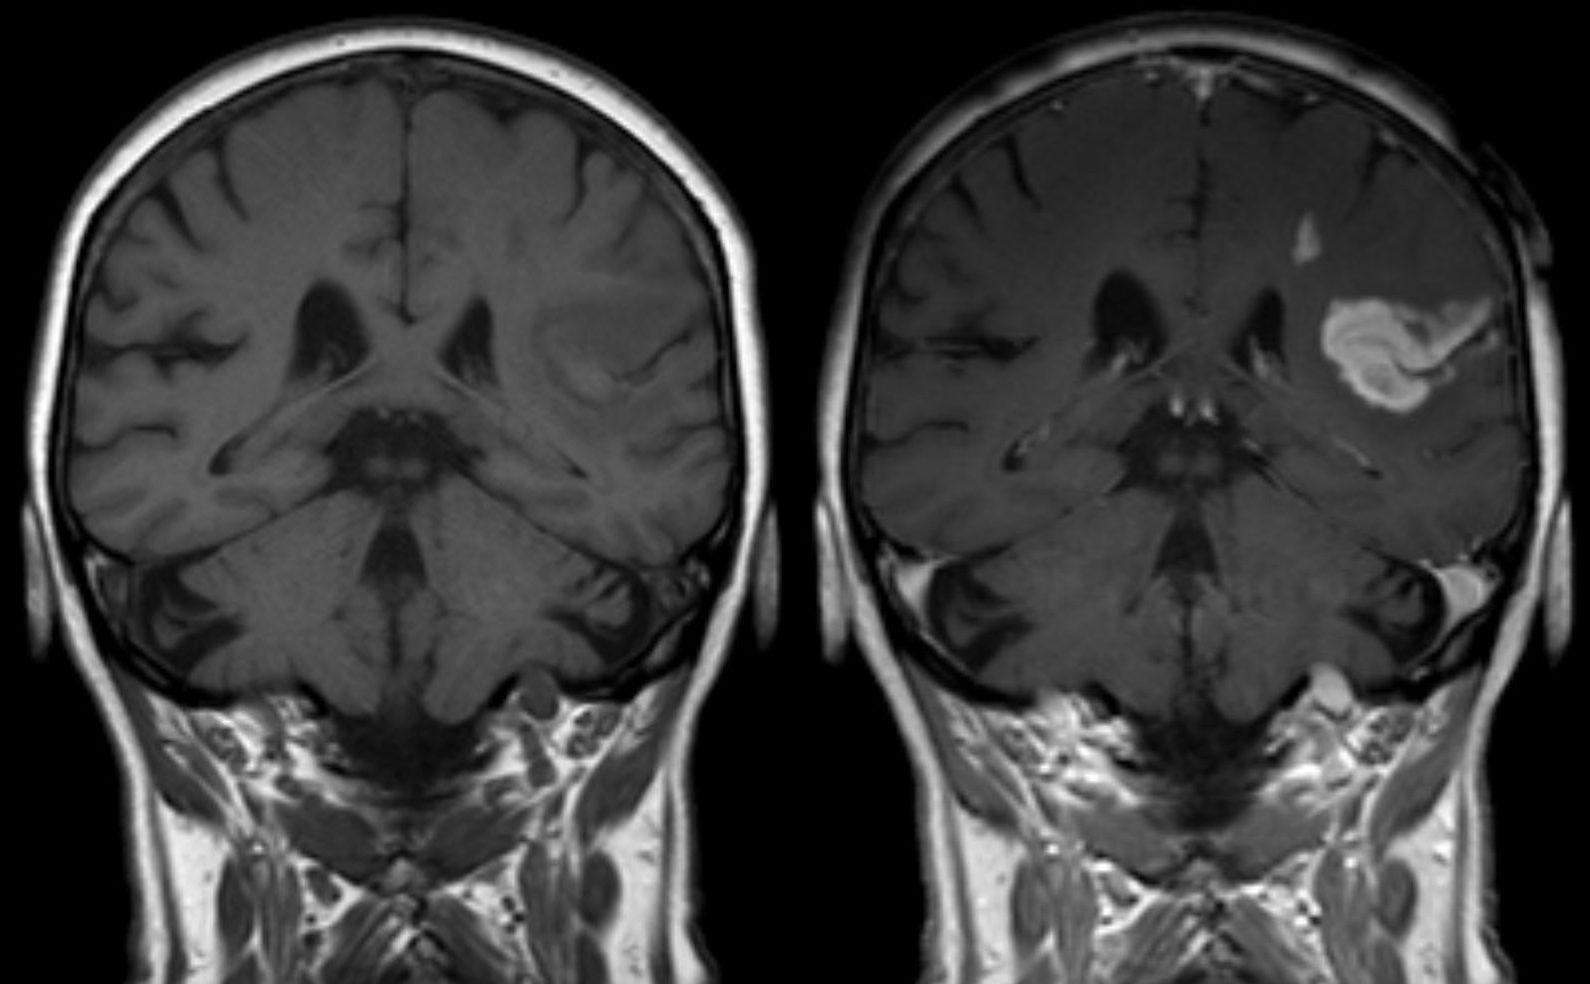

https://case.edu/med/neurology/NR/T1 T1 gad.jpg

MRIs And Contrast Gadolinium Powerful Patient

https://powerfulpatient.org/wp-content/uploads/2018/09/Screen-Shot-2015-10-26-at-8.51.12-PM.png